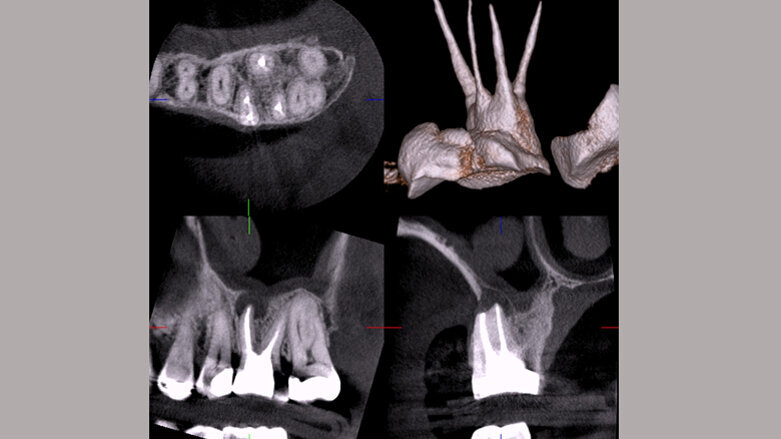

Considero que se tendrían más casos de éxito, menos eventos adversos durante y después de los tratamientos si se realizara el diagnóstico desde una imagen tridimensional, sin desplazar la panorámica que utilizamos para la valoración inicial del paciente, ya que son aplicables sin riesgo de falla en el diagnóstico.

Hoy por hoy, nos enfrentamos a un sinfín de enfermedades, sintomatologías que evolucionan de la misma forma que avanza todo en este nuevo siglo, y como dentistas estamos en la obligación de informar al paciente que muchas enfermedades sistémicas están relacionadas con la cavidad bucal. Por ejemplo, la periodontitis con Alzheimer, diabetes, enfermedades cardíacas; es allí donde las imágenes diagnósticas 3D juegan un papel fundamental como herramienta indispensable en la práctica dental. No es concebible que en este siglo aún nos aferremos a la existencia y utilización de equipamientos análogos y químicos de revelado tóxicos para nuestra salud, que no ayudan al ecosistema del planeta, e imágenes diagnósticas que no parecen ya de este mundo y que disminuyen la capacidad interpretativa del odontólogo.

Las nuevas generaciones de especialistas, más los que ya estamos hace varios años ejerciendo nuestra profesión, debemos promover responsablemente las prácticas seguras de diagnóstico, incluyendo la Tomografía Cone Beam para la evaluación de nuestros pacientes. Y, ahora, con los avances tecnológicos se promueve la imagen Panorámica 2.5D que, sin ser una tomografía, permite evaluar a nuestro paciente en profundidad, y no dejando de lado la radiografía periapical.